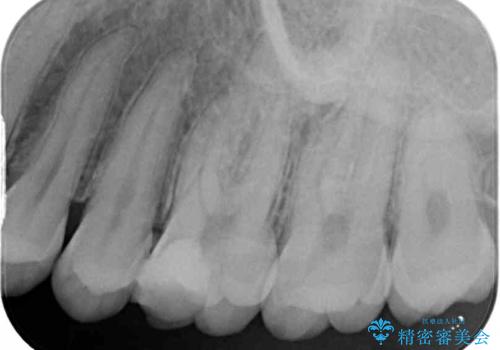

診査をしたところ、レントゲン写真よりとても大きなむし歯があることが分かりました。

虫歯が歯髄腔(神経の部屋)に達している可能性が非常に高かったため、炎症を起こしている神経組織を部分的に切除し、歯根部分の神経組織を保存する治療法が望ましいと考えられました。

処置開始前から神経組織を部分的に除去する可能性が高いことが分かっていたため、ラバーダムなどの環境を整え、無菌的環境下にて処置を進めて行きました。

虫歯は深くまで進行しており、歯冠部の神経から出血が認められました。神経を部分的に除去したところ出血が治まったので、生体親和性の非常に高いセメントにて充填し、仮封をしました。